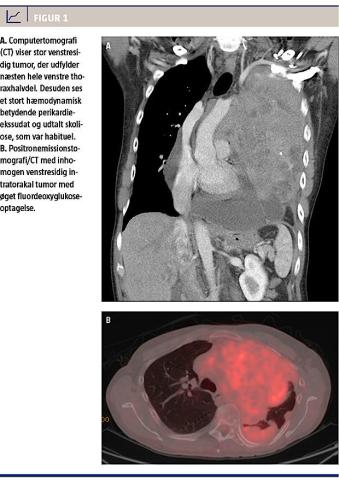

Efter en computertomografi (CT) af thorax og øvre abdomen (Figur 1A) blev der rejst mistanke om malignt pleuramesoteliom pga. en 18 × 10 × 14 cm venstresidig tumor med involvering af pleura samt et 5 cm stort og hæmodynamisk betydende perikardieekssudat. Der blev udført akut perikardiocentese. Perikardievæsken indeholdt ikke malign cytologi. Ved en positronemissionstomografi/CT blev der

påvist øget 18F-fluordeoxyglukoseoptagelse i en uregelmæssig tumorproces, der udfyldte næsten hele venstre thoraxhalvdel (Figur 1B). Patologisvar fra